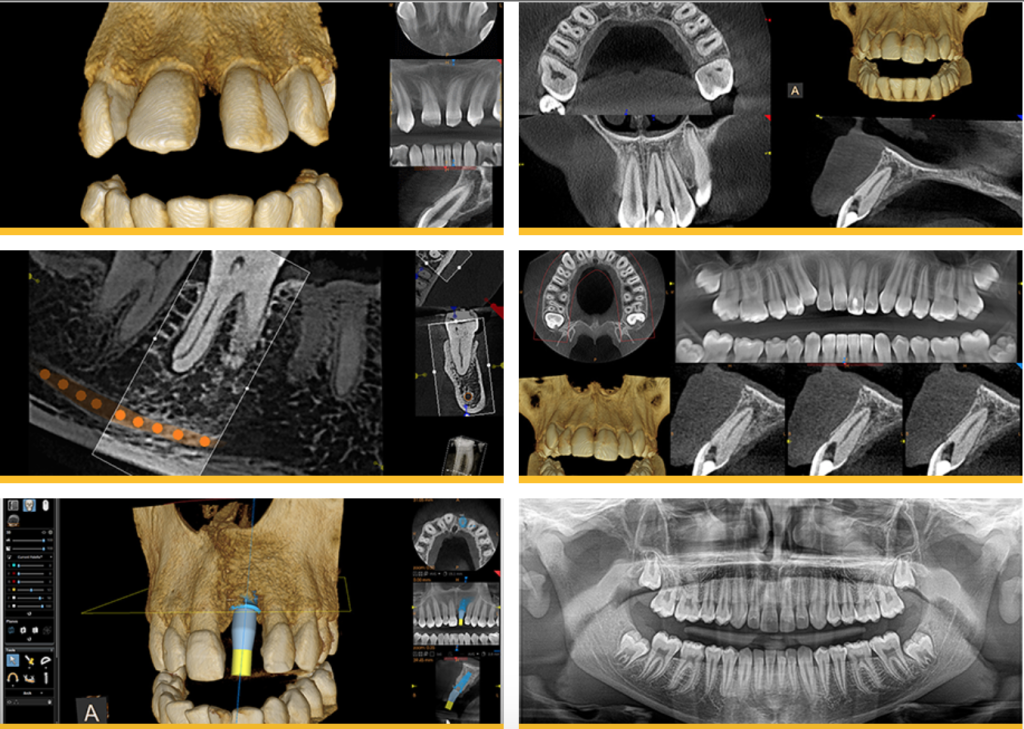

Cone Beam CT Scanning & Virtual Implant Planning

Dental CT 3D imaging is the standard of care in dental implantology. This 3D radiographic image provides a detailed mapping of the anatomy so that implants can be placed more quickly, more accurately, and with a much higher level of comfort and safety. Quality, predictability, and reliability of treatment is our priority at IMPrESS Perio Implant Center. In implant dentistry, we are able to provide all that with the use of the CT scan and planning software in our office.